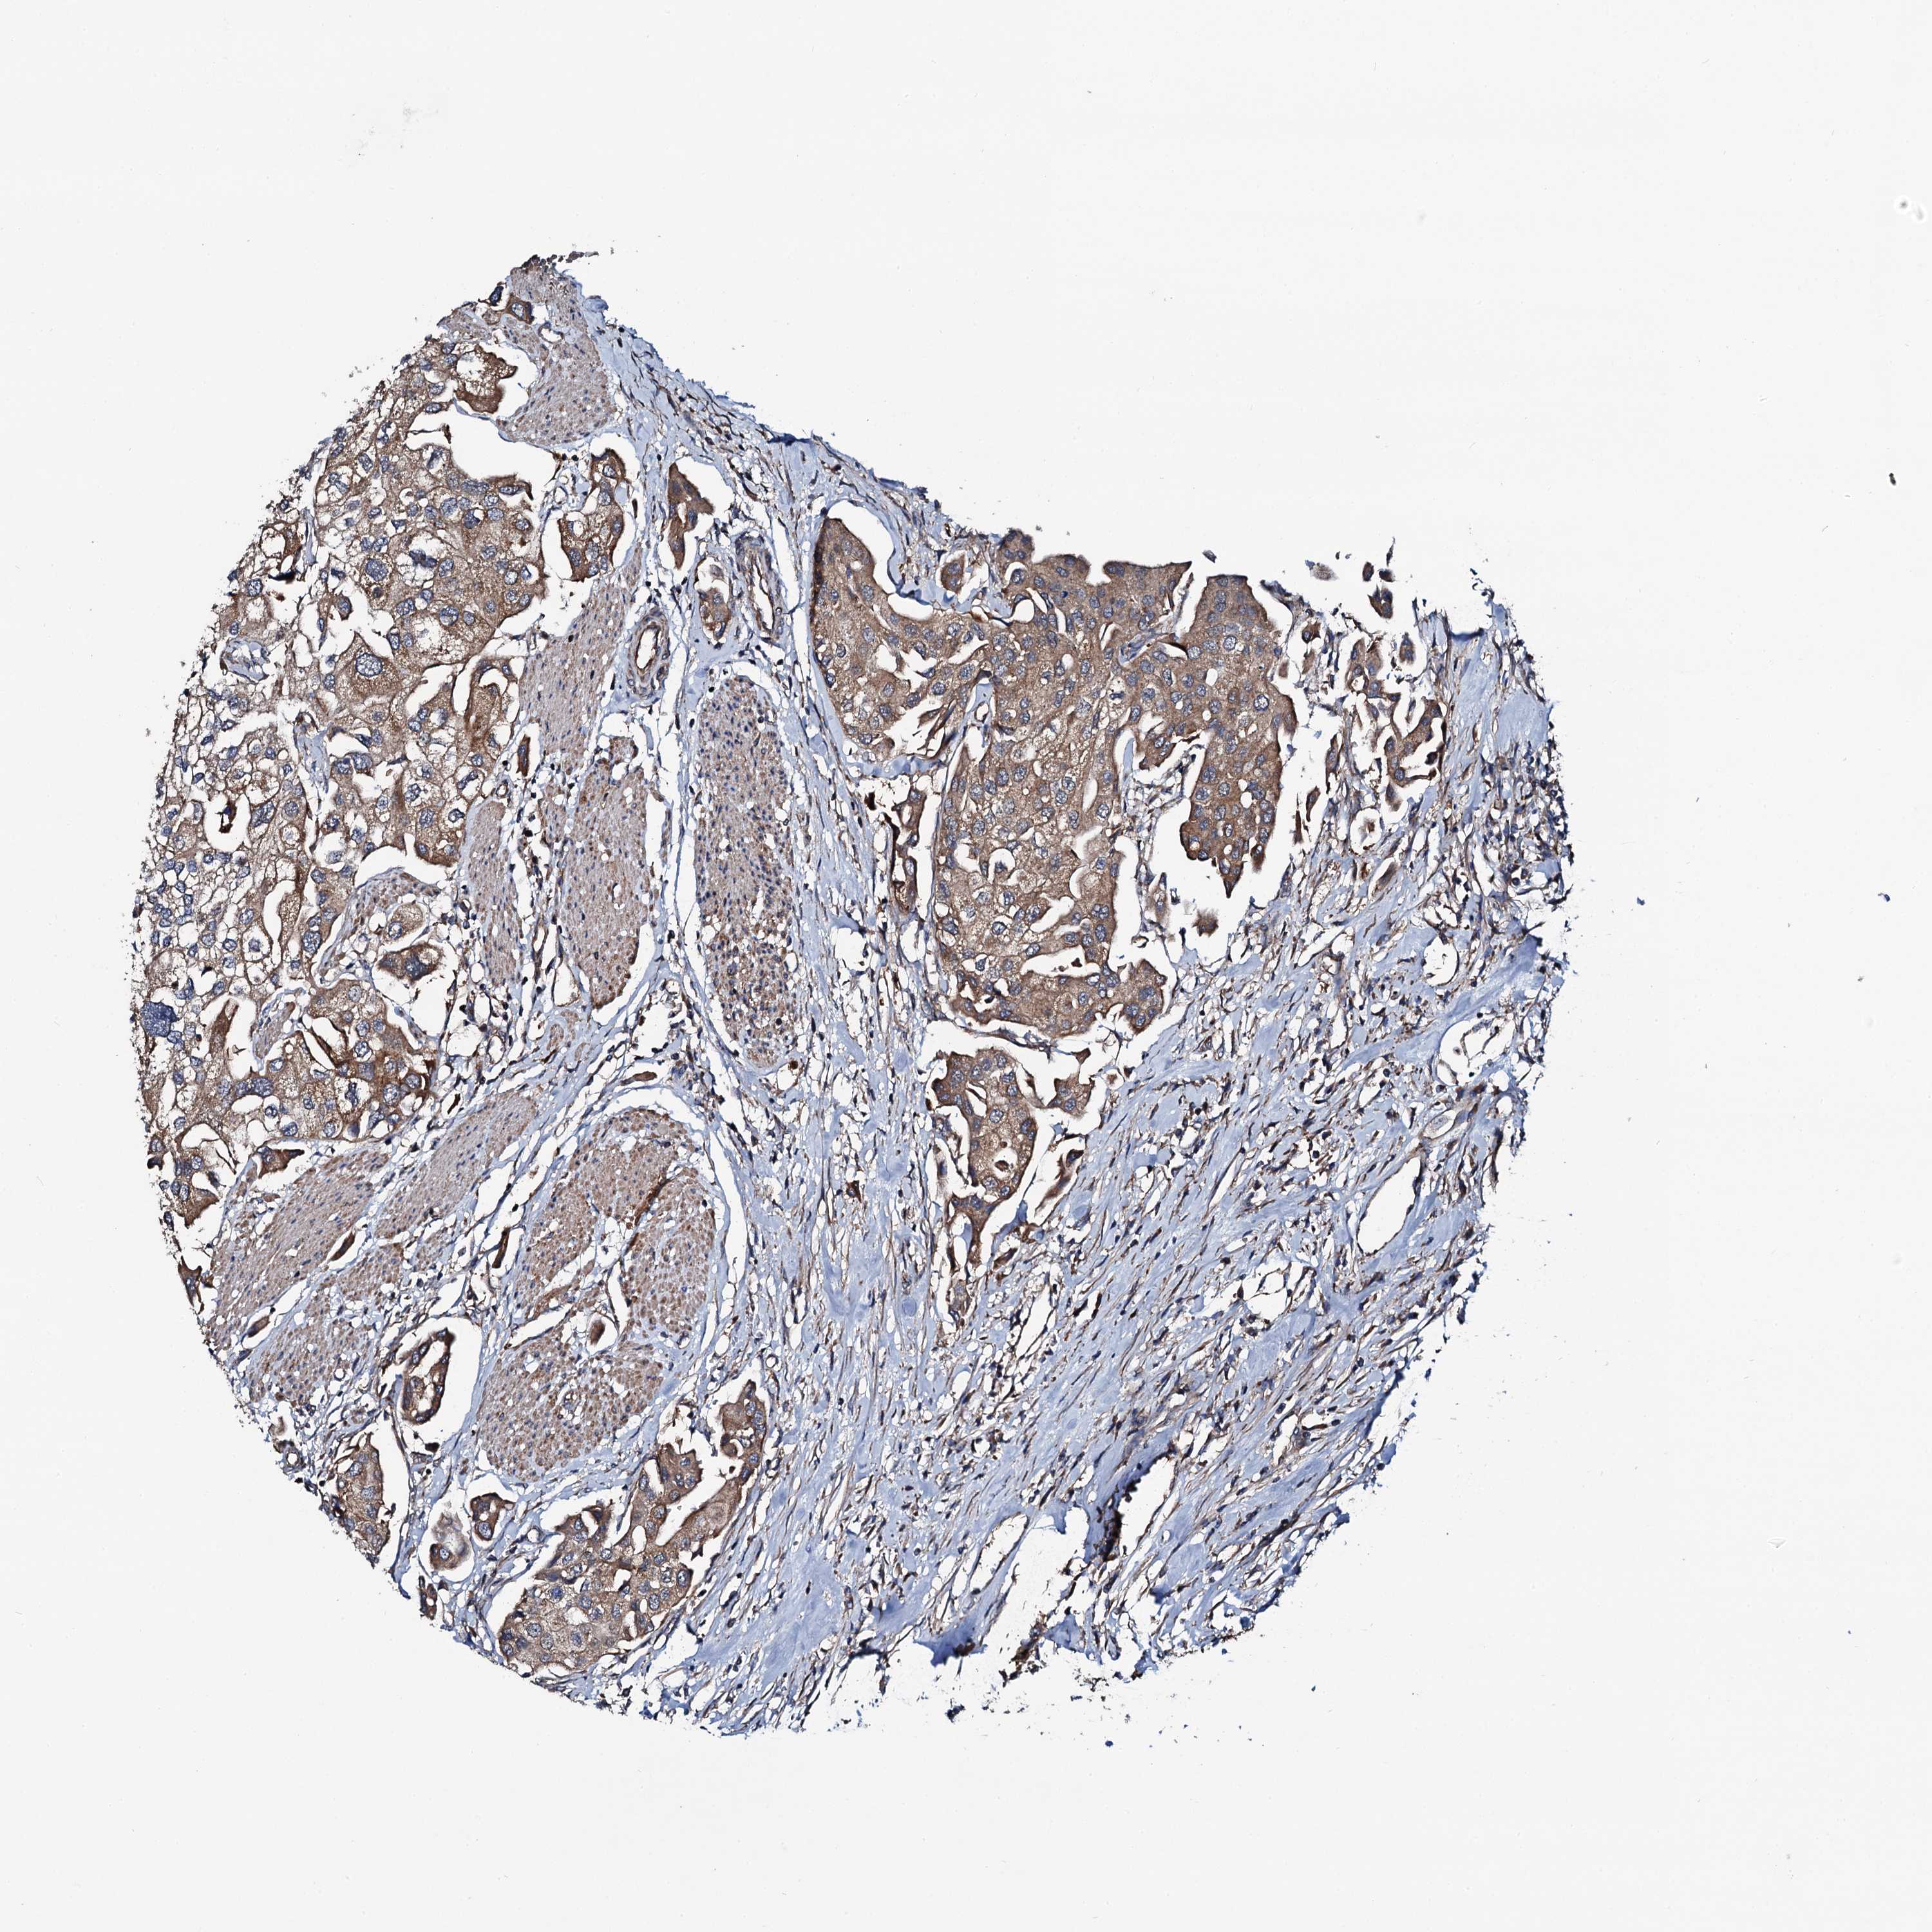

UROTHELIAL CANCER - Protein expressioni

A mouse-over function shows sample information and annotation data. Click on an image to view it in a full screen mode. Samples can be filtered based on level of antibody staining by selecting one or several of the following categories: high, medium, low and not detected. The assay and annotation is described here.

Note that samples used for immunohistochemistry by the Human Protein Atlas do not correspond to samples in the TCGA dataset.

Antibody stainingi

Antibody staining in the annotated cell types in the current human tissue is reported as not detected, low, medium, or high, based on conventional immunohistochemistry profiling in selected tissues. This score is based on the combination of the staining intensity and fraction of stained cells.

Each image is clickable and will lead to virtual microscopy that enables deeper exploration of all samples and also displays staining intensity scores, fraction scores and subcellular localization as well as patient and tissue information for each sample.

Antibody HPA020873

Antibody HPA040413

Urothelial carcinoma, High grade

Urothelial carcinoma, Low grade

Urothelial carcinoma, NOS